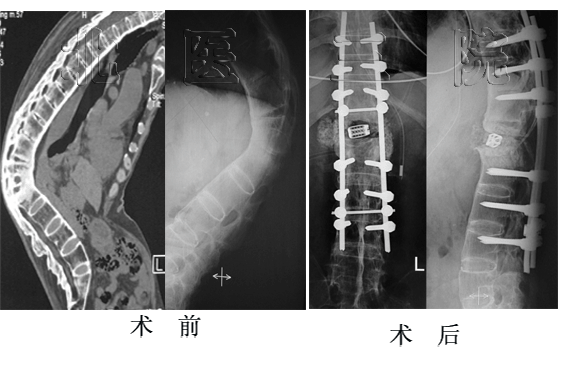

女性,17岁,胸腰段结核性后凸,术前后凸角度130o,经后路矫形术后仅剩37o,矫正率71.5%